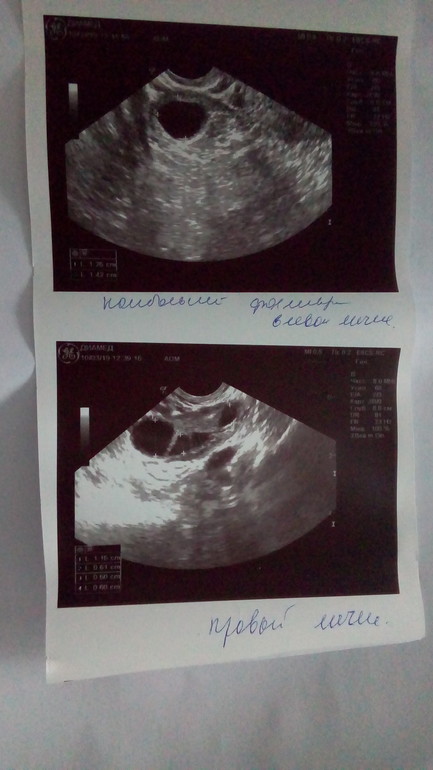

04.03.19г - На 4 день цикла УЗИ:

Эндометрий 4 мм

В Правом Яичнике Персистирующий фолликул 13*12 мм, остальные мелкие фолликулы 4 мм ,4 мм, 3 мм

В Левом Яичнике Фолликулы 5 мм, 4 мм, 4 мм, 3 мм, 3 мм, 3 мм.